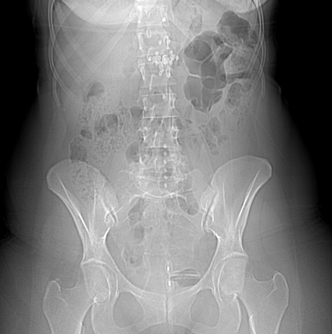

She was stable at admission, and apyretic. Physical examination found a soft abdomen with suprapubic tenderness without defense or contracture. The external urethral meatus was normal. A routine vaginal examination was normal. Cytobacteriological examination of urine (CBEU) found a positive leukocyturia (150 000/ml), microscopic hematuria (42 000/ml), and negative culture. The kidney, ureters, and bladder (KUB) x-ray revealed a T-shaped IUCD on the suprapubic region (Figure 1). Pelvic ultrasonography showed a T-shaped echogenic focus within the bladder. Computed tomography (CT) showed a hyperdense T-shaped material related to calcified IUCD (Figures 2 & 3).

Figure 1 Kidney, ureter, and bladder radiography showing a T-shaped IUCD on the suprapubic region.